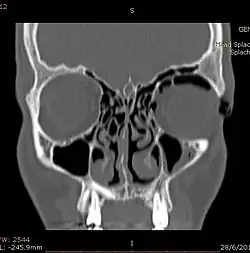

Woman with preorbital swelling in orbital emphysema shown in CT scans

CT scan taken from the coronal plane demonstrating orbital emphysema.[39]

Computed tomography is effective and sensitive in the diagnosis of orbital emphysema,[3][37] as it can confirm the anatomical location and size of air, bony defects, indentation of the eyeball, and the condition of the optic nerve, as well as the presence of any extraocular muscle entrapment and herniation of preorbital fat into the sinus cavities.[3][15][38] The location of the orbital emphysema is present near the site of the fracture.[1][3] The scans are usually taken along the transverse plane. Transverse images allow the evaluation of fractures in medial and lateral orbital walls. By reformatting these transverse images or taking coronal images, the examination of orbital floor and roof is permitted. Helical scanning is preferred as it has a lower imaging time and radiation dose comparing to conventional scanning, especially when reforming transverse helical scans into coronal images.[3] The staging of orbital emphysema can then be determined with visual acuity examination and ophthalmoscopy.[6] A disadvantage of using a CT scan is that when detecting air after orbital trauma, the presence of a wooden foreign object can give a false positive result of orbital emphysema. The wooden object can mimic the presence of orbital emphysema. Therefore, patients’ medical history is crucial in making the correct diagnosis.[3]